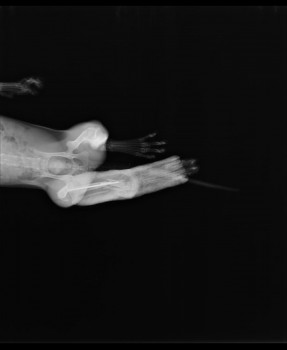

История закончилась хорошо. Кость срослась, спица в ней никак не мешает движению и не дала осложнений.

На снимке - состояние через 80 дней после операции.

Хочу отметить, что в Подольске все клиники используют только метод остеосинтеза спицами. Если перелом со множеством осколков, то фиксировать их лучше другими методами, то есть придётся везти животное в клинику в другой город.